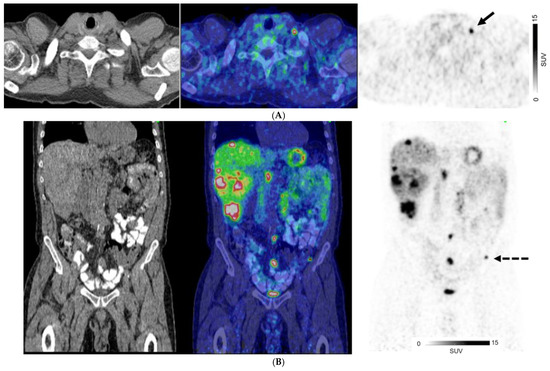

Figure 2.

A 67-year-old man with well-differentiated G1 small bowel NET, Ki 67 = 3% metastatic to liver. Staging CT showed mid-ileal tumor, regional nodal metastases, and bilobar liver metastases [CT stage: n1M1a]. 68Ga-DOTATATE PET/CT (A,B) Axial and Coronal—CT (left), fused PET/CT (middle) and PET (right); (C) Sagittal—Fused PET/CT (left) and PET (right) shows in addition, extrahepatic metastases including extraregional nodes including supraclavicular and cardiophrenic nodes (arrows in (A,C)), and peritoneal metastases (dotted arrows in (B,C)); overall, PET stage: n1M1c.